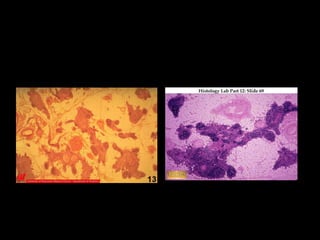

TONZILETONZILE

Tonzile su strateški raspoređene u usnoj dupljiTonzile su strateški raspoređene u usnoj duplji

da spreče ulazak bakterija, virusa tj. antigenada spreče ulazak bakterija, virusa tj. antigena

Tonzile su uvlačenja površinskog epitelaTonzile su uvlačenja površinskog epitela

(KRIPTE) oko koga su grupisani agregati(KRIPTE) oko koga su grupisani agregati

limfnog tkiva, a koje su delimičnolimfnog tkiva, a koje su delimično

inkapsulisaneinkapsulisane

Limfnoepitelna kooperacijaLimfnoepitelna kooperacija

Primarni i sekundarni limfni folikuli suPrimarni i sekundarni limfni folikuli su prisutniprisutni

Waldejerov prsten od tonzila -limfnog tkivaWaldejerov prsten od tonzila -limfnog tkiva

 na ulazu u orofaringsna ulazu u orofarings

–– Adenoidi: krov faringsaAdenoidi: krov faringsa

–– Palatinalne tonzile: faringsni lukoviPalatinalne tonzile: faringsni lukovi

–– Lingualna tonzila: baza jezikaLingualna tonzila: baza jezika

–– Tonsilae tubarie: bočne straneTonsilae tubarie: bočne strane

faringsafaringsa